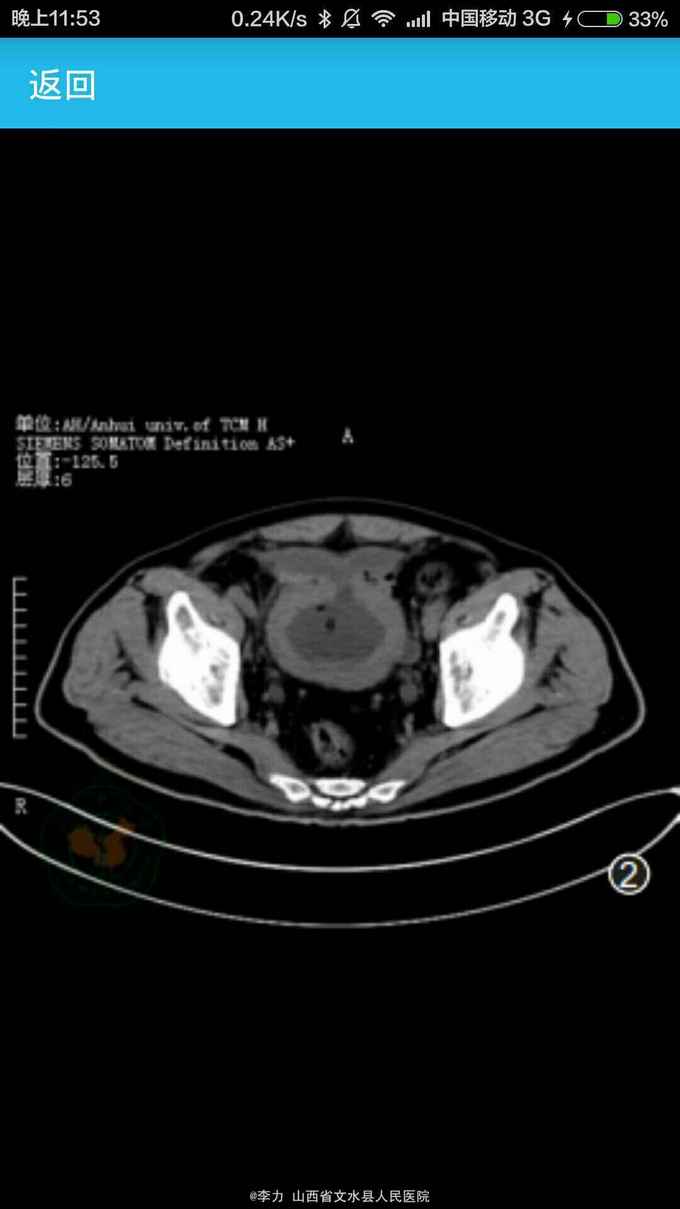

诊断前列腺增生。 入院后予以留置导尿,硬膜外麻醉下行经尿道前列腺等离子电切术。术中见前列腺中叶、两侧叶均明显增生,突向膀胱内呈球形。 电切过程中用Ellik冲洗器冲出组织碎片。当电切膀胱颈顶部时闻及爆炸声,立即怀疑膀胱内气体爆炸并停止电切。镜下检视膀胱发现前壁有一直径约25px破裂口。因患者一般情况良好,各项生命体征平稳,无明显腹胀、腹肌紧张,故降低冲洗速度,继续修整切除前列腺尖部增生腺体。术后留置导尿、缓慢膀胱冲洗。术后CT检查显示膀胱前壁有一破裂口,位于腹膜外(图2)。患者恢复良好,10d后拔除导尿管,自行排尿通畅。